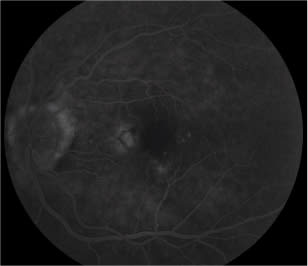

Preferential hyperacuity perimetry showed an abnormality (Figure 1), and conversion to CNV was confirmed by OCT (Figure 2) and IVFA (Figure 3). Fundus photography (Figure 4) showed an area of hemorrhage nasal to the fovea, but no obvious subretinal fluid or subretinal exudate. Using PHP, we were able to rule out vision impairment due to cataracts and our retina specialist started treatment for wet AMD. After treatment with bevacizumab (Avastin, Genentech), triamcinolone acetonide and bevacizumab again, each one month apart, the patient's metamorphopsia in the left eye resolved. If her CNV had gone undetected any longer, it is likely she would not have had such a successful outcome.

Figure 3. Fluorescein angiography identifies a classic choroidal neovascularization that corresponds precisely to the scotoma identified with PHP.